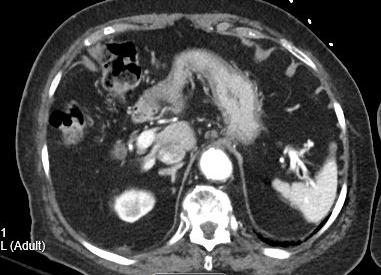

Our patient had a multicystic lesion in the head of the pancreas suggestive of a serous cystic neoplasm.  She also had multiple cystic pancreatic tail lesions thought to represent intraductal papillary neoplasms.  In addition, she had a renal sinus cyst on the left which can mimic hydronephrosis.